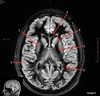

Image weighting and axis

T2 Flair

Sagittal

A

Basal Ganglia

B

Posterior horn lateral ventricle